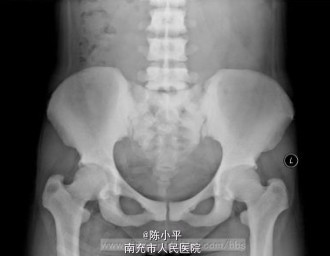

氟骨症一例

氟骨症

患者女,37岁,颈部不适检查时发现,加拍骨盆片,可见纱布眼状骨纹理,未见“同心环”影及腰椎“夹心蛋糕”征,结合职业史,诊断为氟骨症。